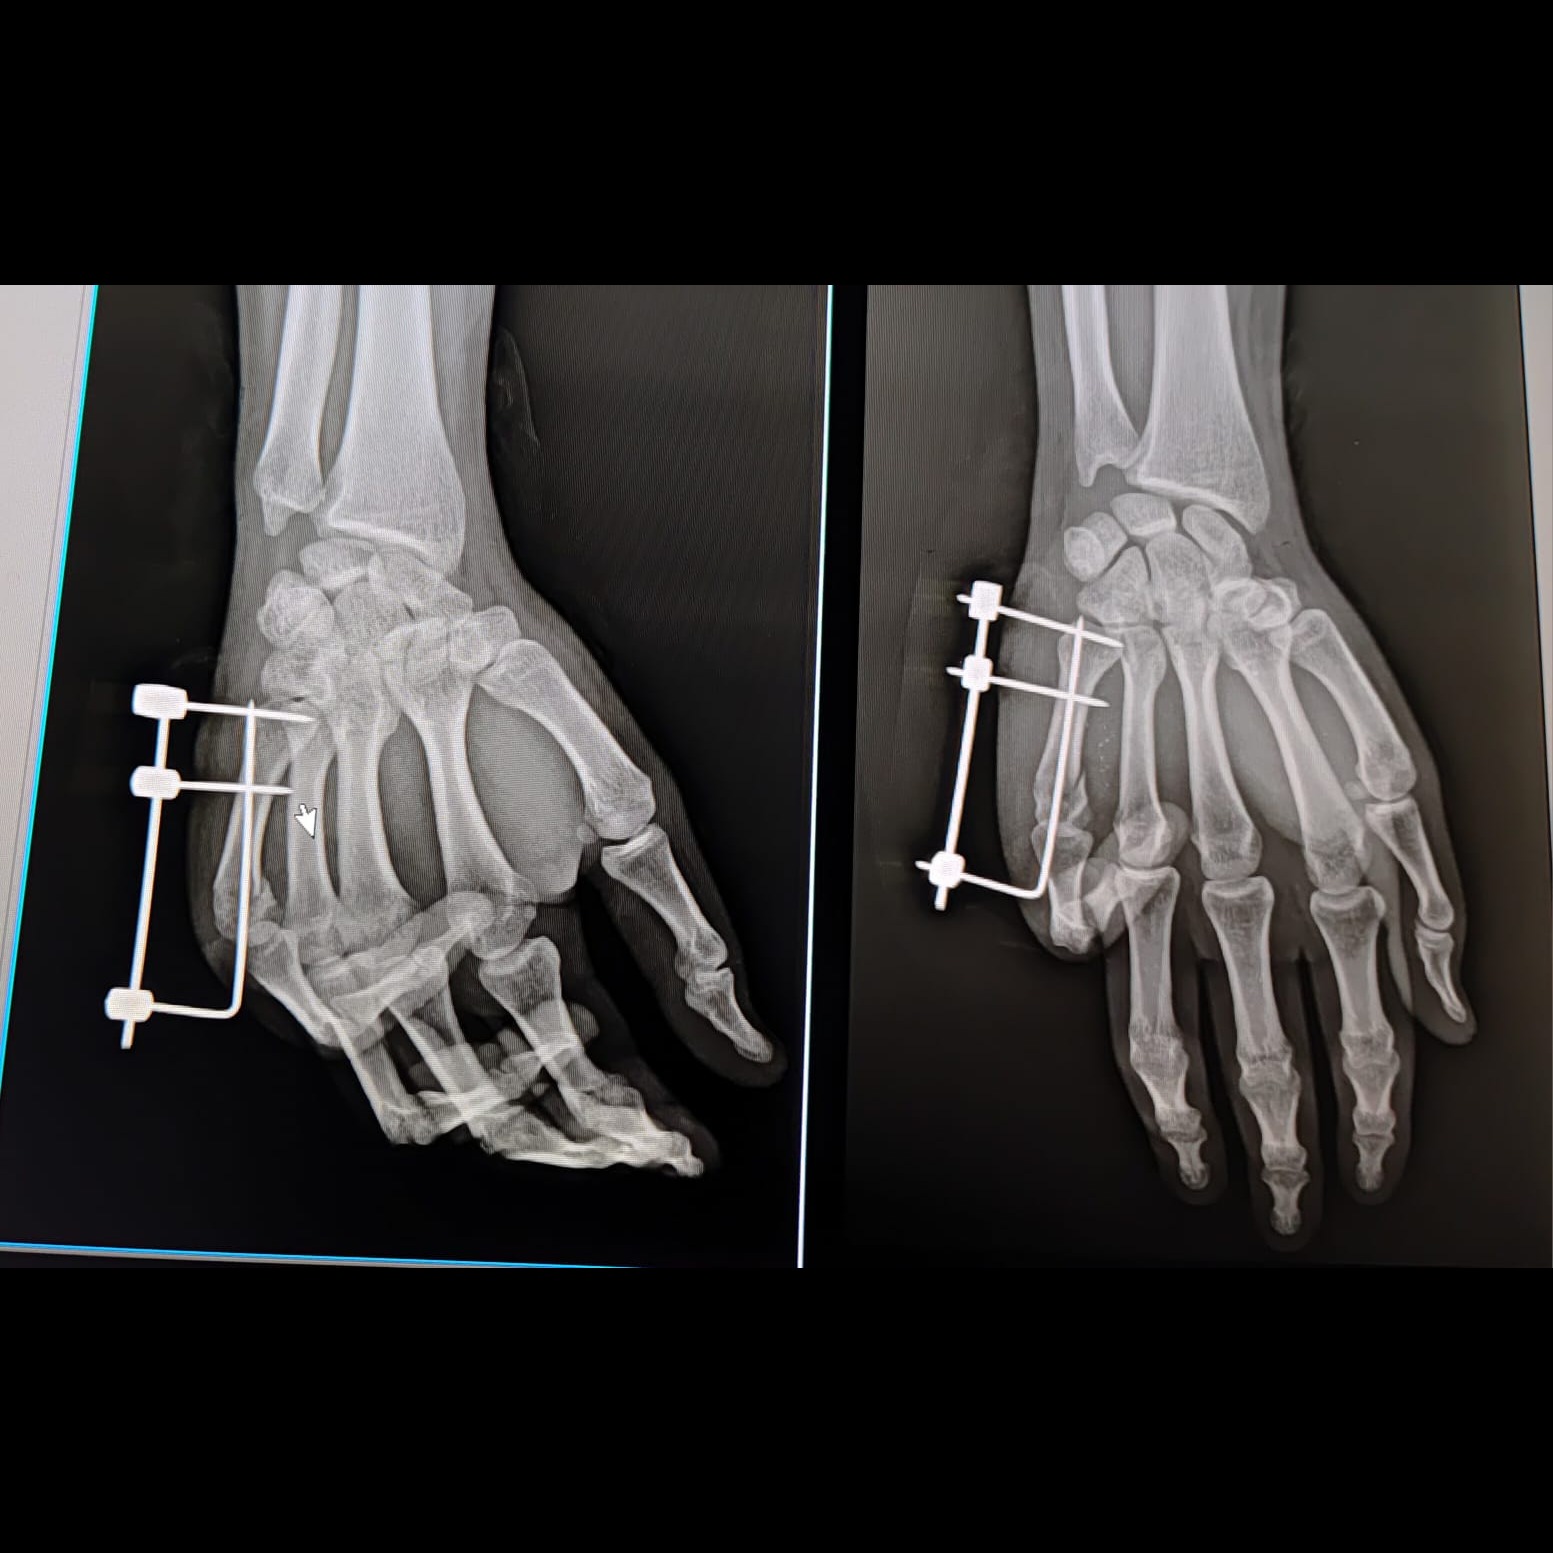

Fifth metacarpal fracture fixed with JESS fixator..No post operative finger stiffness,early recover...